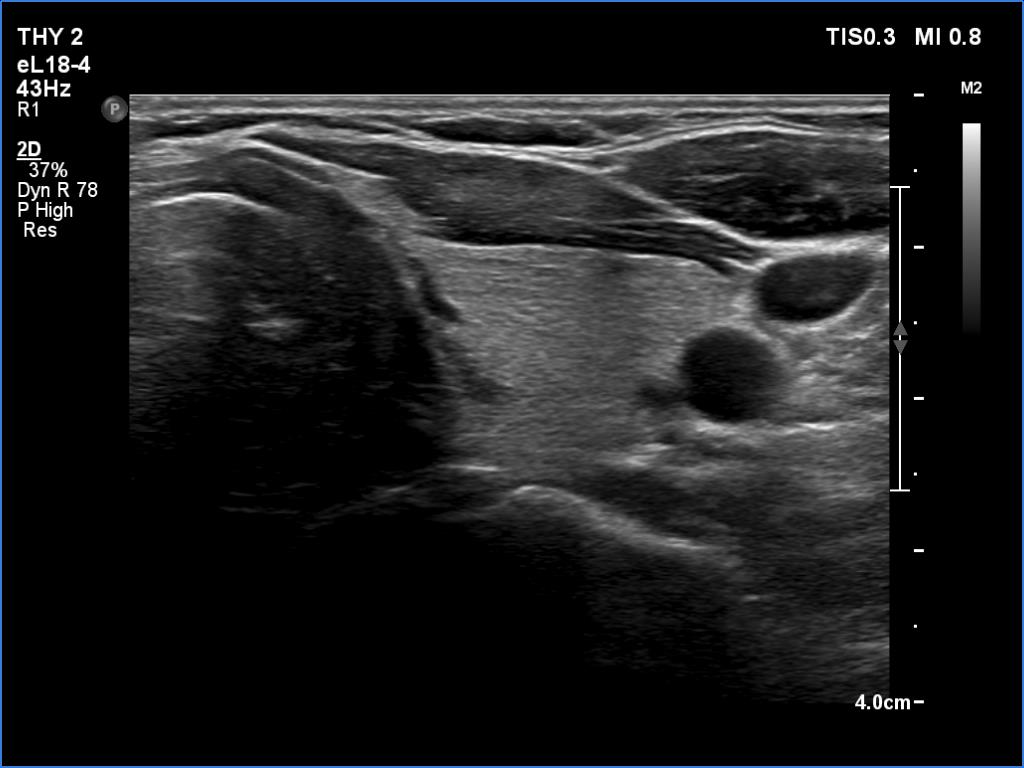

Initial examination (first row of images):

Clinical presentation: A 39-year-old woman was referred for evaluation of neck complaints lasting for more than a month. The patient had fever, neck pain. She has got two courses of antibiotics and non-steroid anti inflammatory drugs which had no effect.

Palpation: The right lobe was painful and hard while the left lobe was tender.

Laboratory examination: TSH 0.01 mIU/L, FT4 29.1 pM/L, FT3 7.45 pM/L, CRP 31.2 mg/L.

Ultrasonography: The thyroid presented with hypoechoic areas which had blurred borders. The echogenicity index was approximately 65% in the right and 20% in the left lobe. The thyroid was almost completely avascular.

Diagnosis: subacute, granulomatous de Quervain's thyroiditis.